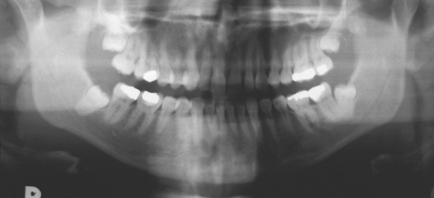

Fig. 5.1 Panoramic radiograph showing impacted lower left wisdom tooth.

Note that the inferior dental nerve canal casts a dark band over the roots of this tooth.